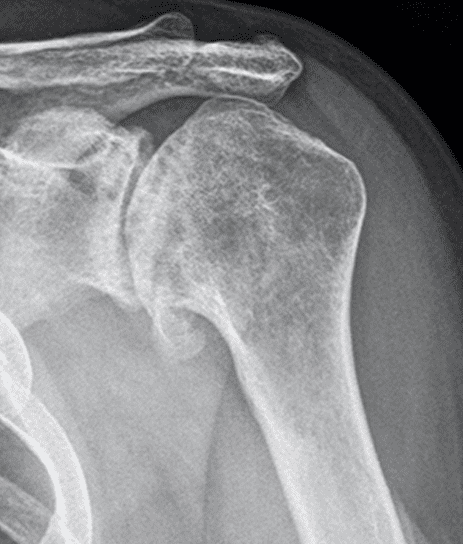

Patient Cases

For fracture and revision treatment

The system offers a set of modular Proximal Bodies in several sizes and heights to be paired with a broad range of Modular Stems, available in different diameters and lengths as well as different surface and coating options for cemented and cementless fixation.

The Proximal Bodies’ spiked surface, together with m-l and a-p holes for suture fixation, allow for stable and physiologic tuberosities reattachment. The modular concept of the fracture components supports the surgeon in achieving adequate joint restoration even in cases with poor anatomical landmarks.1